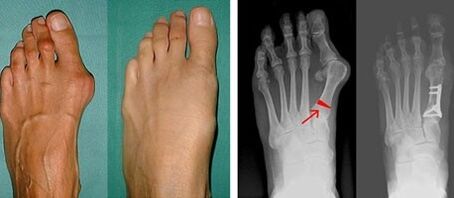

Die Valgusdeformität des ersten Zehs betrifft am häufigsten Frauen im reifen Alter, aber auch Männer. Eine deformierte Daumenbasis sieht ästhetisch nicht ansprechend aus. In diesem Fall verspürt die Person körperliche Beschwerden und im fortgeschrittenen Stadium Schmerzen. Eine Abweichung des großen Zehs ist die Folge einer ungleichmäßigen Körperbelastung des Fußes. Solche Veränderungen wirken sich nachteilig auf die Füße und andere Finger aus.

In der ersten Phase der Valguserkennung des großen und kleinen Zehs führt der Arzt eine visuelle Untersuchung durch. Auf diese Weise wird der Entwicklungsstand der Pathologie bestimmt. Um detaillierte Gelenkveränderungen zu erkennen, werden Röntgenaufnahmen und Plantographie verordnet.

Wenn die visuelle Untersuchung und das Röntgen kein Ergebnis liefern, wird der Patient zur Plantographie überwiesen, um mögliche Plattfüße festzustellen. Bei dieser Methode werden Abdrücke der Füße angefertigt, auf deren Grundlage für den Patienten Schuhe oder Einlagen mit orthopädischen Eigenschaften angefertigt werden. Dem Patienten wird dann eine Podometrie verschrieben. Bei dieser Methode wird mithilfe einer Computeranalyse der Gewichtsdruck einer Person auf die Füße ermittelt. Die Ergebnisse der fortgeschrittenen Diagnostik sind die Grundlage für die Wahl einer Behandlungsmethode bei der Krümmung der ersten und zweiten Zehe.